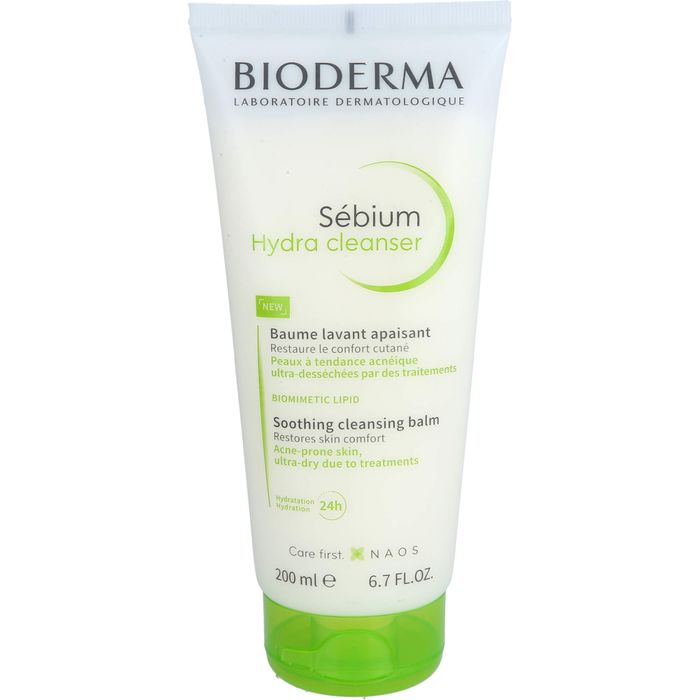

19375435Marke

BIODERMAArtikelnummer/PZN

19375435Marke

BIODERMAArtikelbeschreibung

Wie wirkt es?

- Spendet intensiv Feuchtigkeit

- Lindert unangenehme Spannungsgefühle

- Hautberuhigend und entzündungshemmend

- Lindert Rötungen

- Therapiebegleitend bei der oralen dermatologischen Aknebehandlungen

- Unterstützend bei Spätakne

Bei trockener Mischhaut, Spätakne und therapiebegleitend geeignet.

Besonders während einer oralen Aknetherapie ist die Haut meist sehr gereizt und trocken. Sébium Hydra unterstützt die stark strapaziert Haut mit patentierten Wirkprinzipien und ihrer feuchtigkeitsspendenden Wirkung.

Die Pflege beugt weiteren Hautirritationen vor, lindert Entzündungen und wirkt hautberuhigend.

Die Haut wird nachhaltig reiner und kommt wieder in ihr natürliches Gleichgewicht.

Morgens und/oder abends auf das mit Sébium Gel moussant (Schaumgel) oder Sébium H2O (Mizellenwasser) gereinigte Gesicht auftragen. Bis zum Einziehen sanft einmassieren.

| EAN | 03701129809273 |

| PZN | 19375435 |

| Anbieter | NAOS Deutschland GmbH |

| Packungsgröße | 200 ml |

| Darreichungsform | Gel |